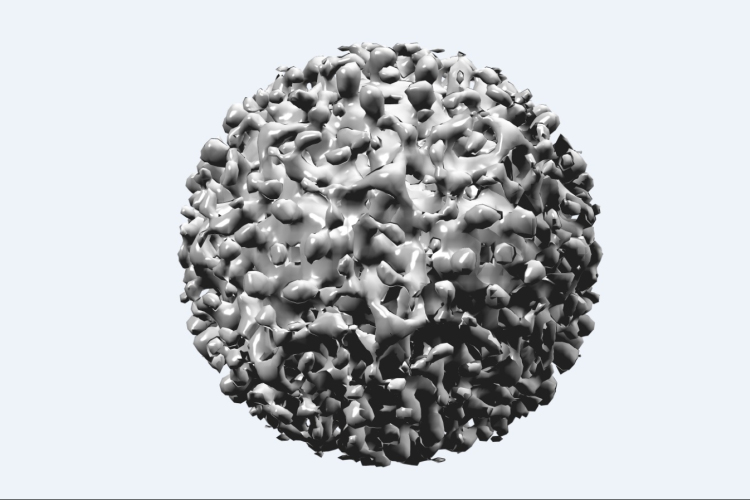

Ingyenes hepatitis C-szűrés lesz az országban több helyen

A Vírusos Májbetegek Országos Egyesülete (Vimor) szeptember 15-én, szombaton országos szűrést szervez a hepatitis C vírussal fertőzöttek felderítésére.